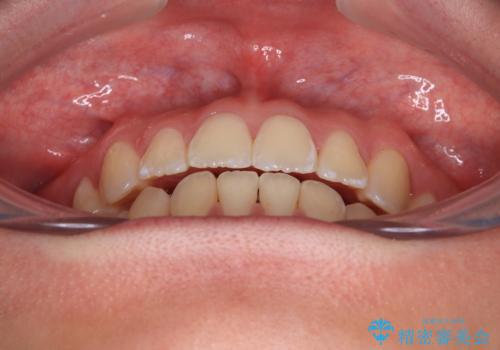

前歯が2本ない ワイヤー装置での抜歯矯正

- 下顎前歯欠損による隙間と、上顎前歯の突出感を気にして来院された患者様です。

横顔に出っ歯の印象はありませんでしたが、下顎のスペースと上下前歯の前後位置の大きなズレを改善するために、上顎左右の第一小臼歯2本を抜歯しすることとしました。

口元が引っ込みすぎることもなく、上下前歯がきれいに接触する位置に仕上げることができました。